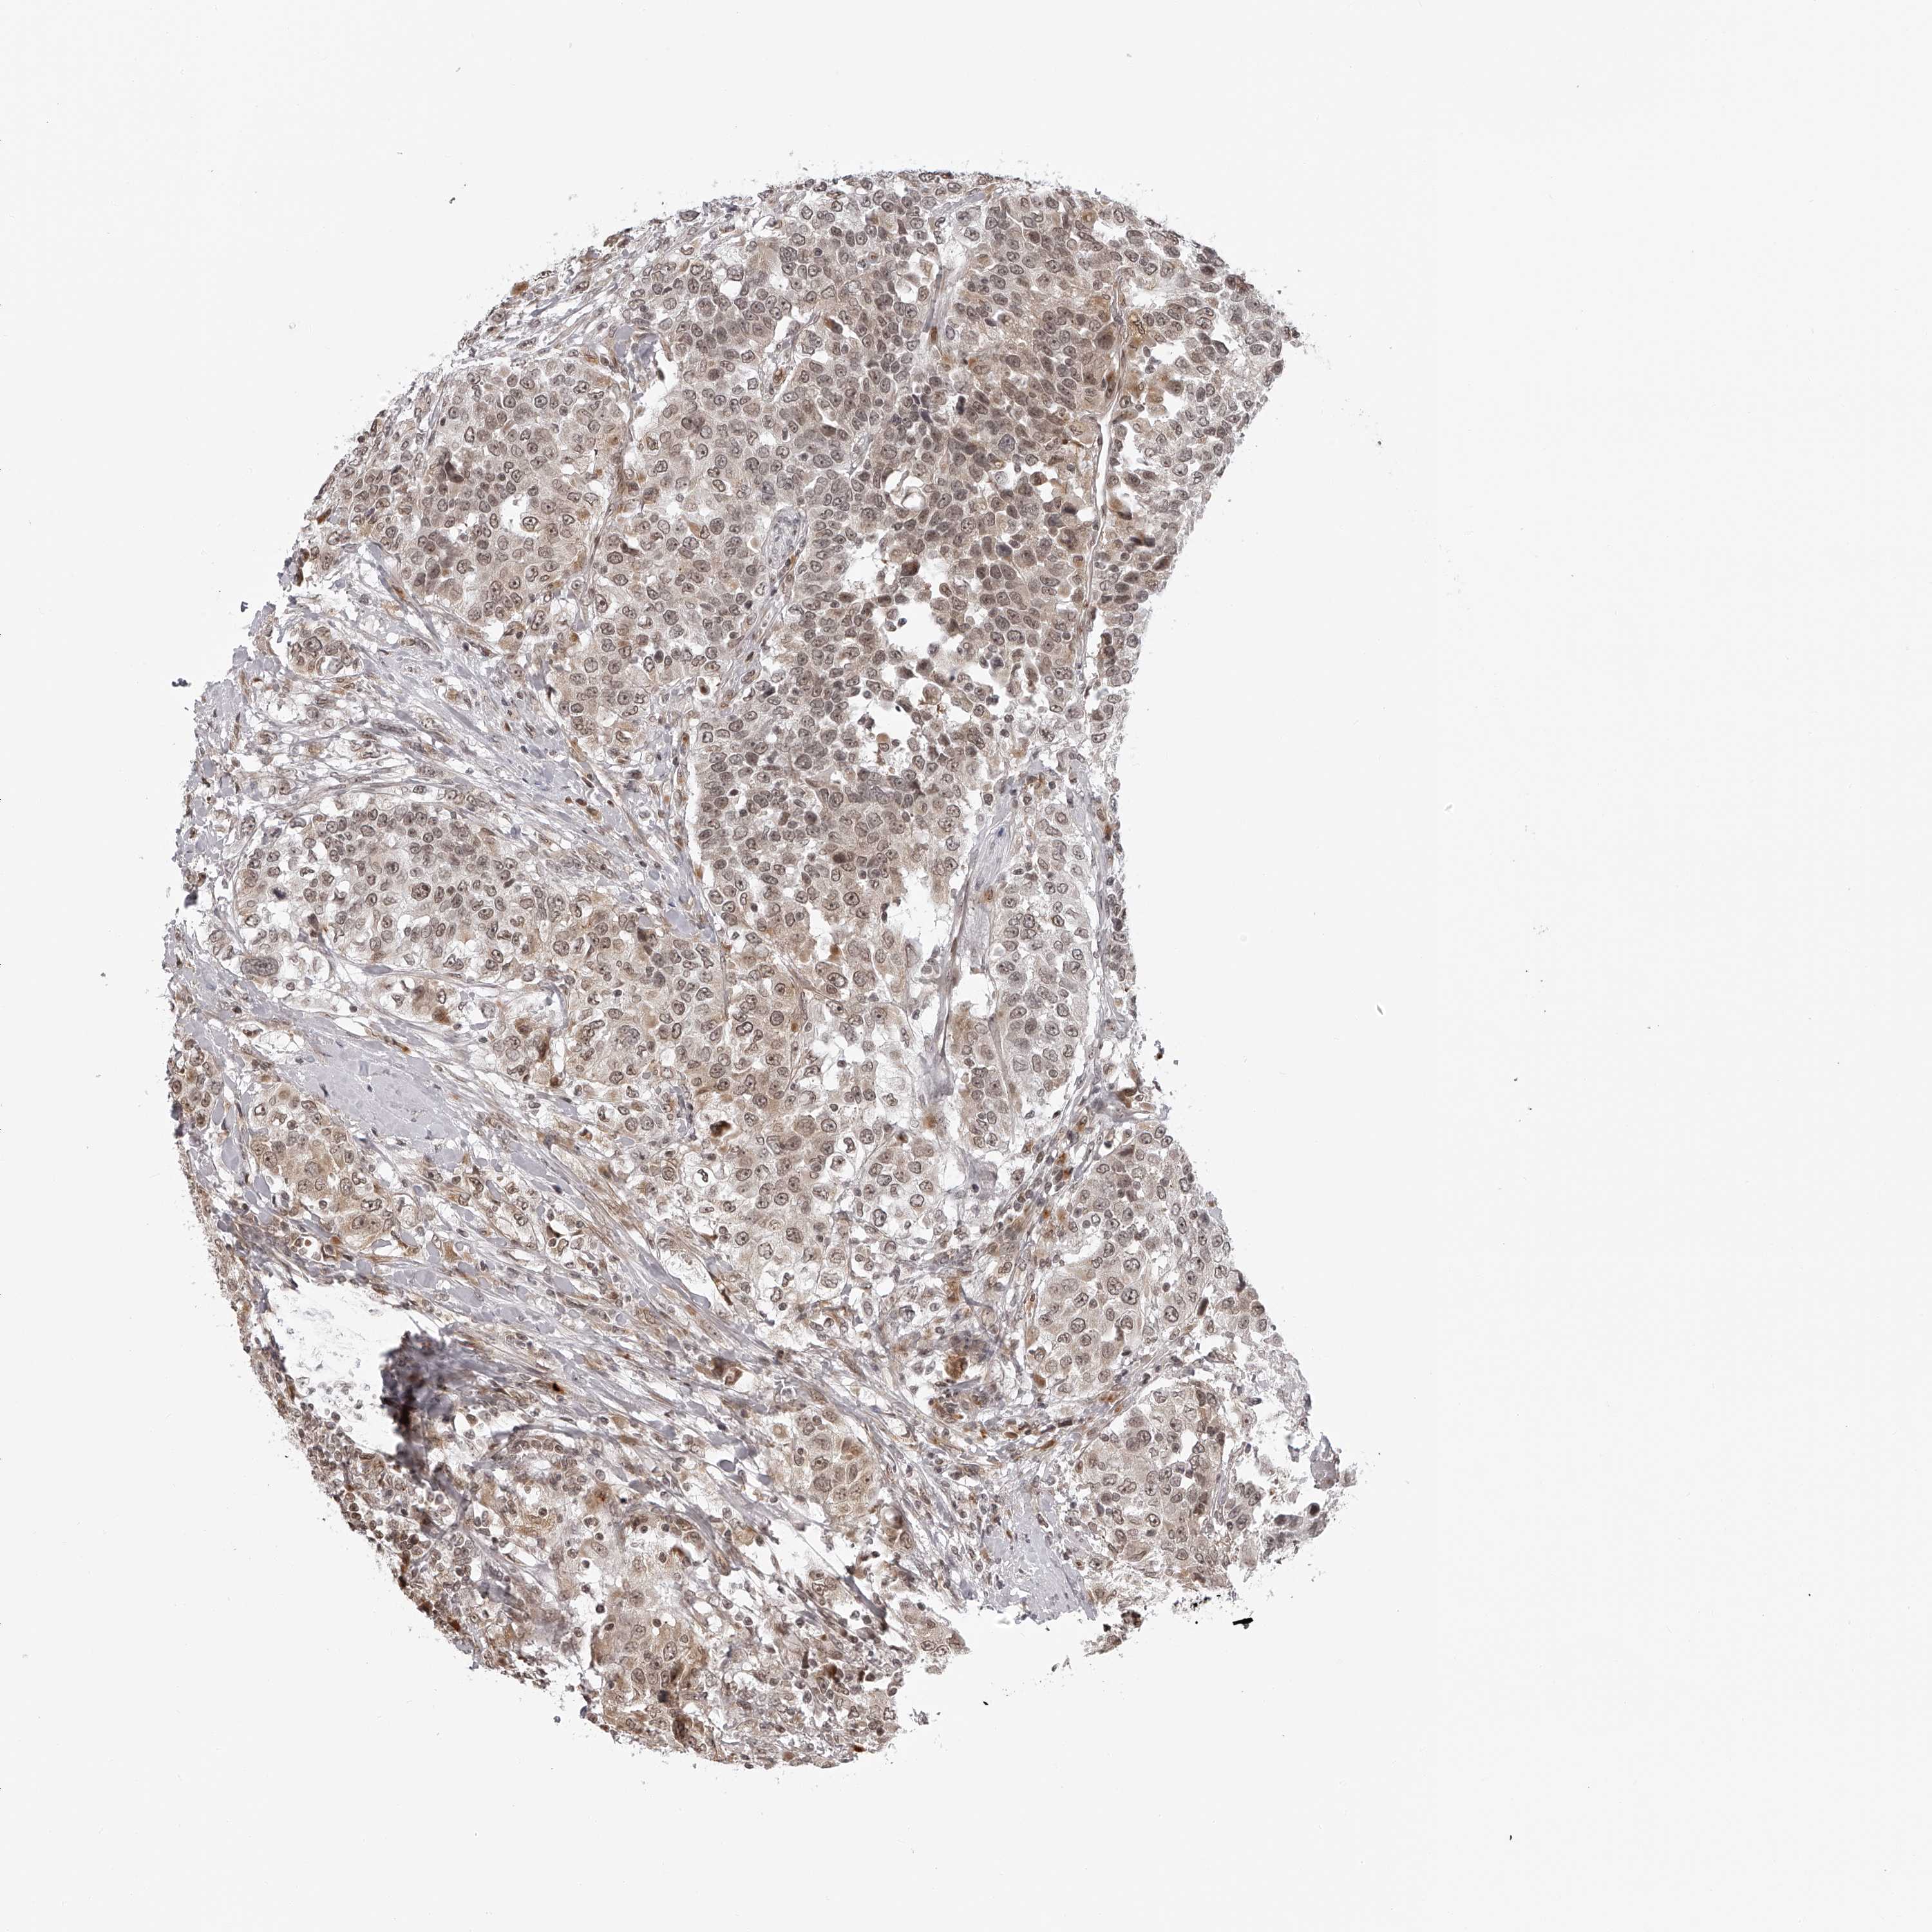

UROTHELIAL CANCER - Protein expressioni

A mouse-over function shows sample information and annotation data. Click on an image to view it in a full screen mode. Samples can be filtered based on level of antibody staining by selecting one or several of the following categories: high, medium, low and not detected. The assay and annotation is described here.

Note that samples used for immunohistochemistry by the Human Protein Atlas do not correspond to samples in the TCGA dataset.

Antibody stainingi

Antibody staining in the annotated cell types in the current human tissue is reported as not detected, low, medium, or high, based on conventional immunohistochemistry profiling in selected tissues. This score is based on the combination of the staining intensity and fraction of stained cells.

Each image is clickable and will lead to virtual microscopy that enables deeper exploration of all samples and also displays staining intensity scores, fraction scores and subcellular localization as well as patient and tissue information for each sample.

Antibody HPA028020

Antibody HPA028095

Antibody HPA028333

Urothelial carcinoma, Low grade

Urothelial carcinoma, High grade